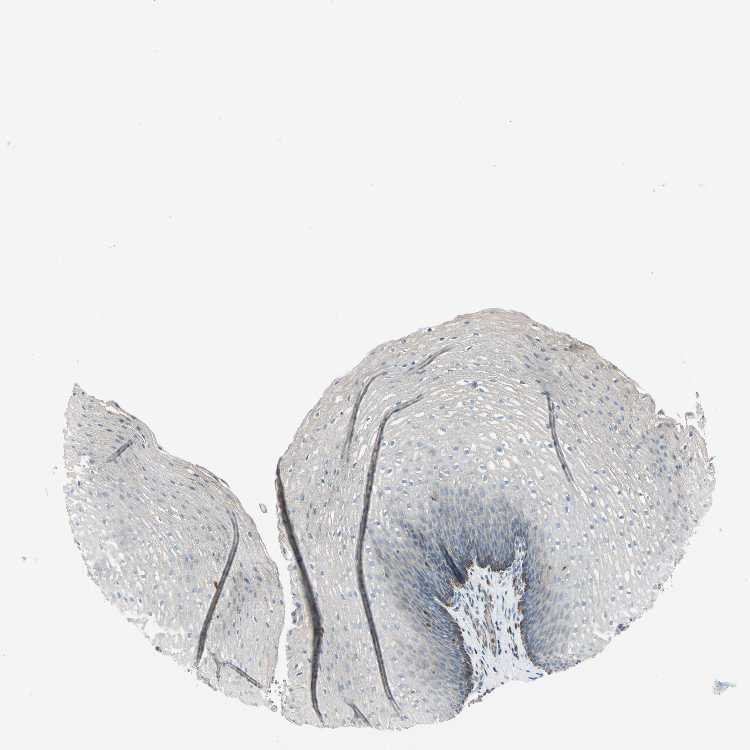

ESOPHAGUS - Antibody stainingi

Antibody staining in the annotated cell types in the current human tissue is reported as not detected, low, medium, or high, based on conventional immunohistochemistry profiling in selected tissues. This score is based on the combination of the staining intensity and fraction of stained cells.

Each image is clickable and will lead to virtual microscopy that enables deeper exploration of all samples and also displays staining intensity scores, fraction scores and subcellular localization as well as patient and tissue information for each sample.

Antibody HPA009076

Squamous epithelial cells Low